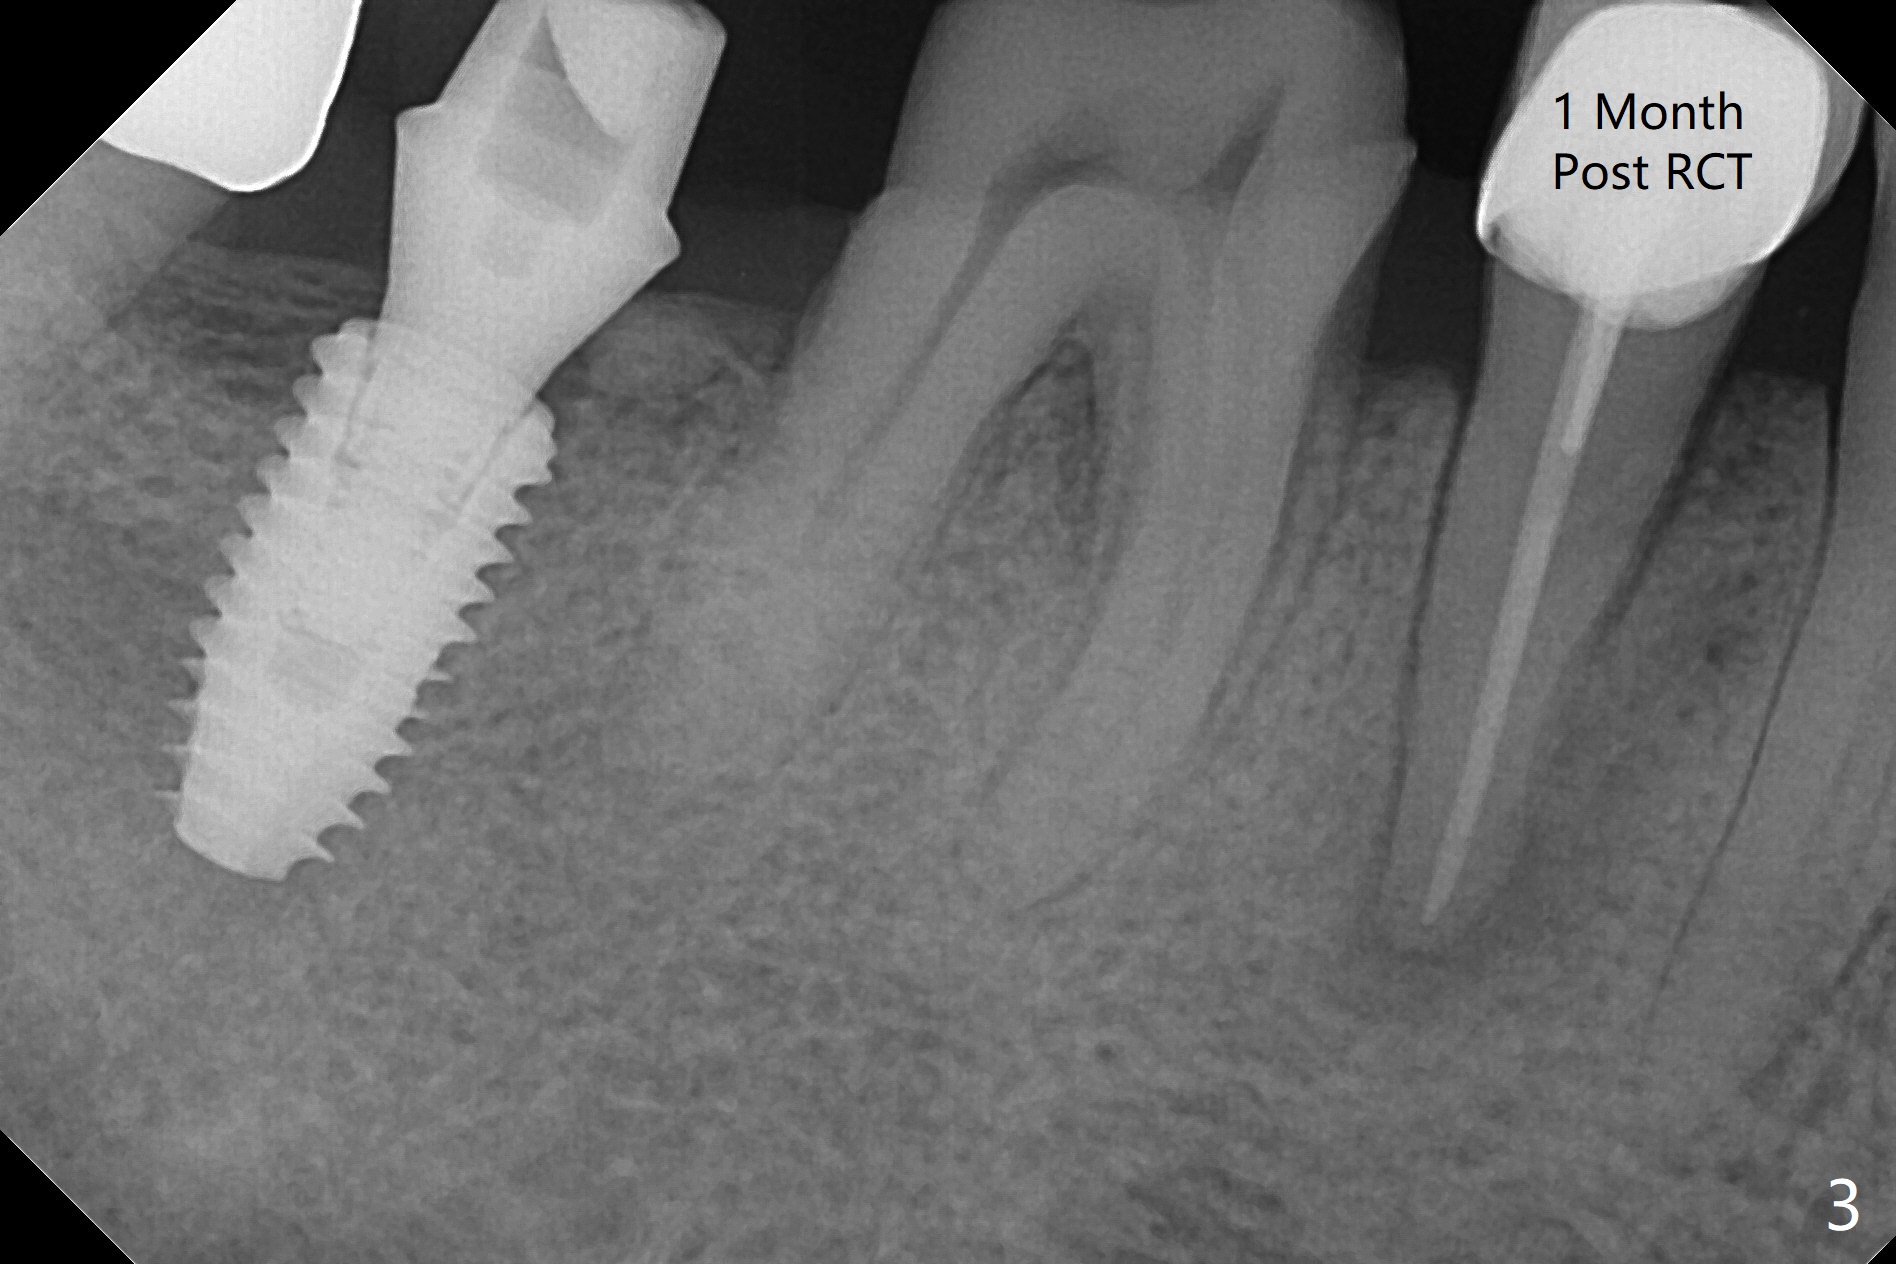

While the guided implant at #19 is osteointegrating, porcelain chips in the mesial marginal ridge of the retainer at #30 (Fig.2 *), causing food impaction between #29 and 30. The units #30 and 31 are removed. Impression is taken for guide at #31 (Fig.1). A temporary crown is fabricated for #30. Since there is sufficient bone, a 5x11.5 mm implant will be placed (Fig.1). If mouth opening is limited, a 10 mm long will be used. RCT will be done for the tooth #29 first for the buccal fistula (Fig.2). The fistula disappears 1 month post RCT (Fig.3,4 <) when a 5x10 mm implant is placed at #31.